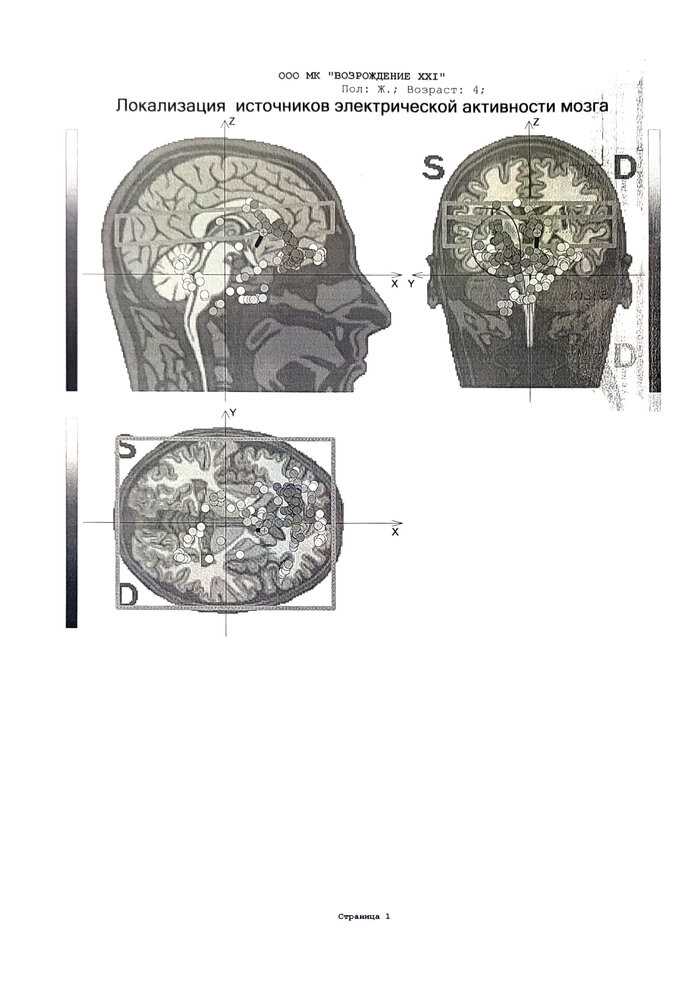

Наш врач назначила нам ЭЭГ дневного сна в клинике Возрождение (г. Уссурийск).

Тем не менее, исследование провели и прислали результат. Супруга очень переживает, хотя, по факту там ничего плохого не написано. Она отправила результаты врачу. Врач молчит. Жена нервничает.

Если на пикабу есть человек, который способен и имеет возможность дать комментарии по исследованию, прошу отписаться в комментариях. Во-первых, цель - немного успокоить жену. Во-вторых, разобраться с тем, что видно в исследовании. В-третьих, определиться с планом дальнейших действий.